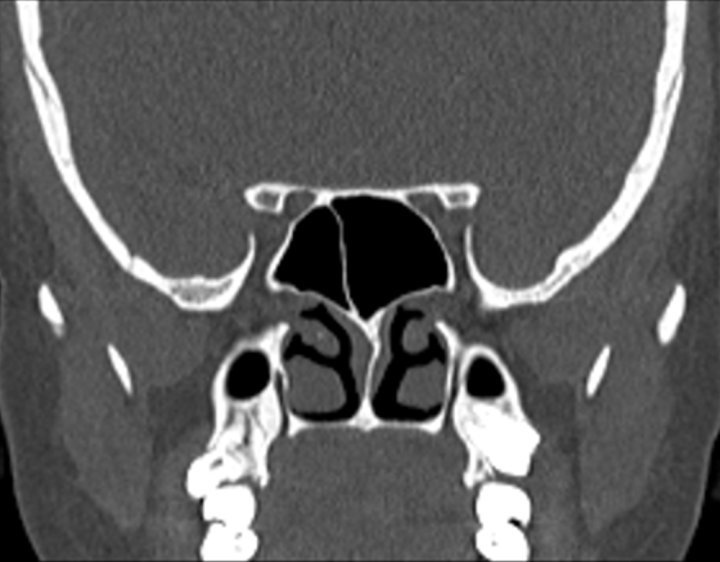

Click any image for labels.